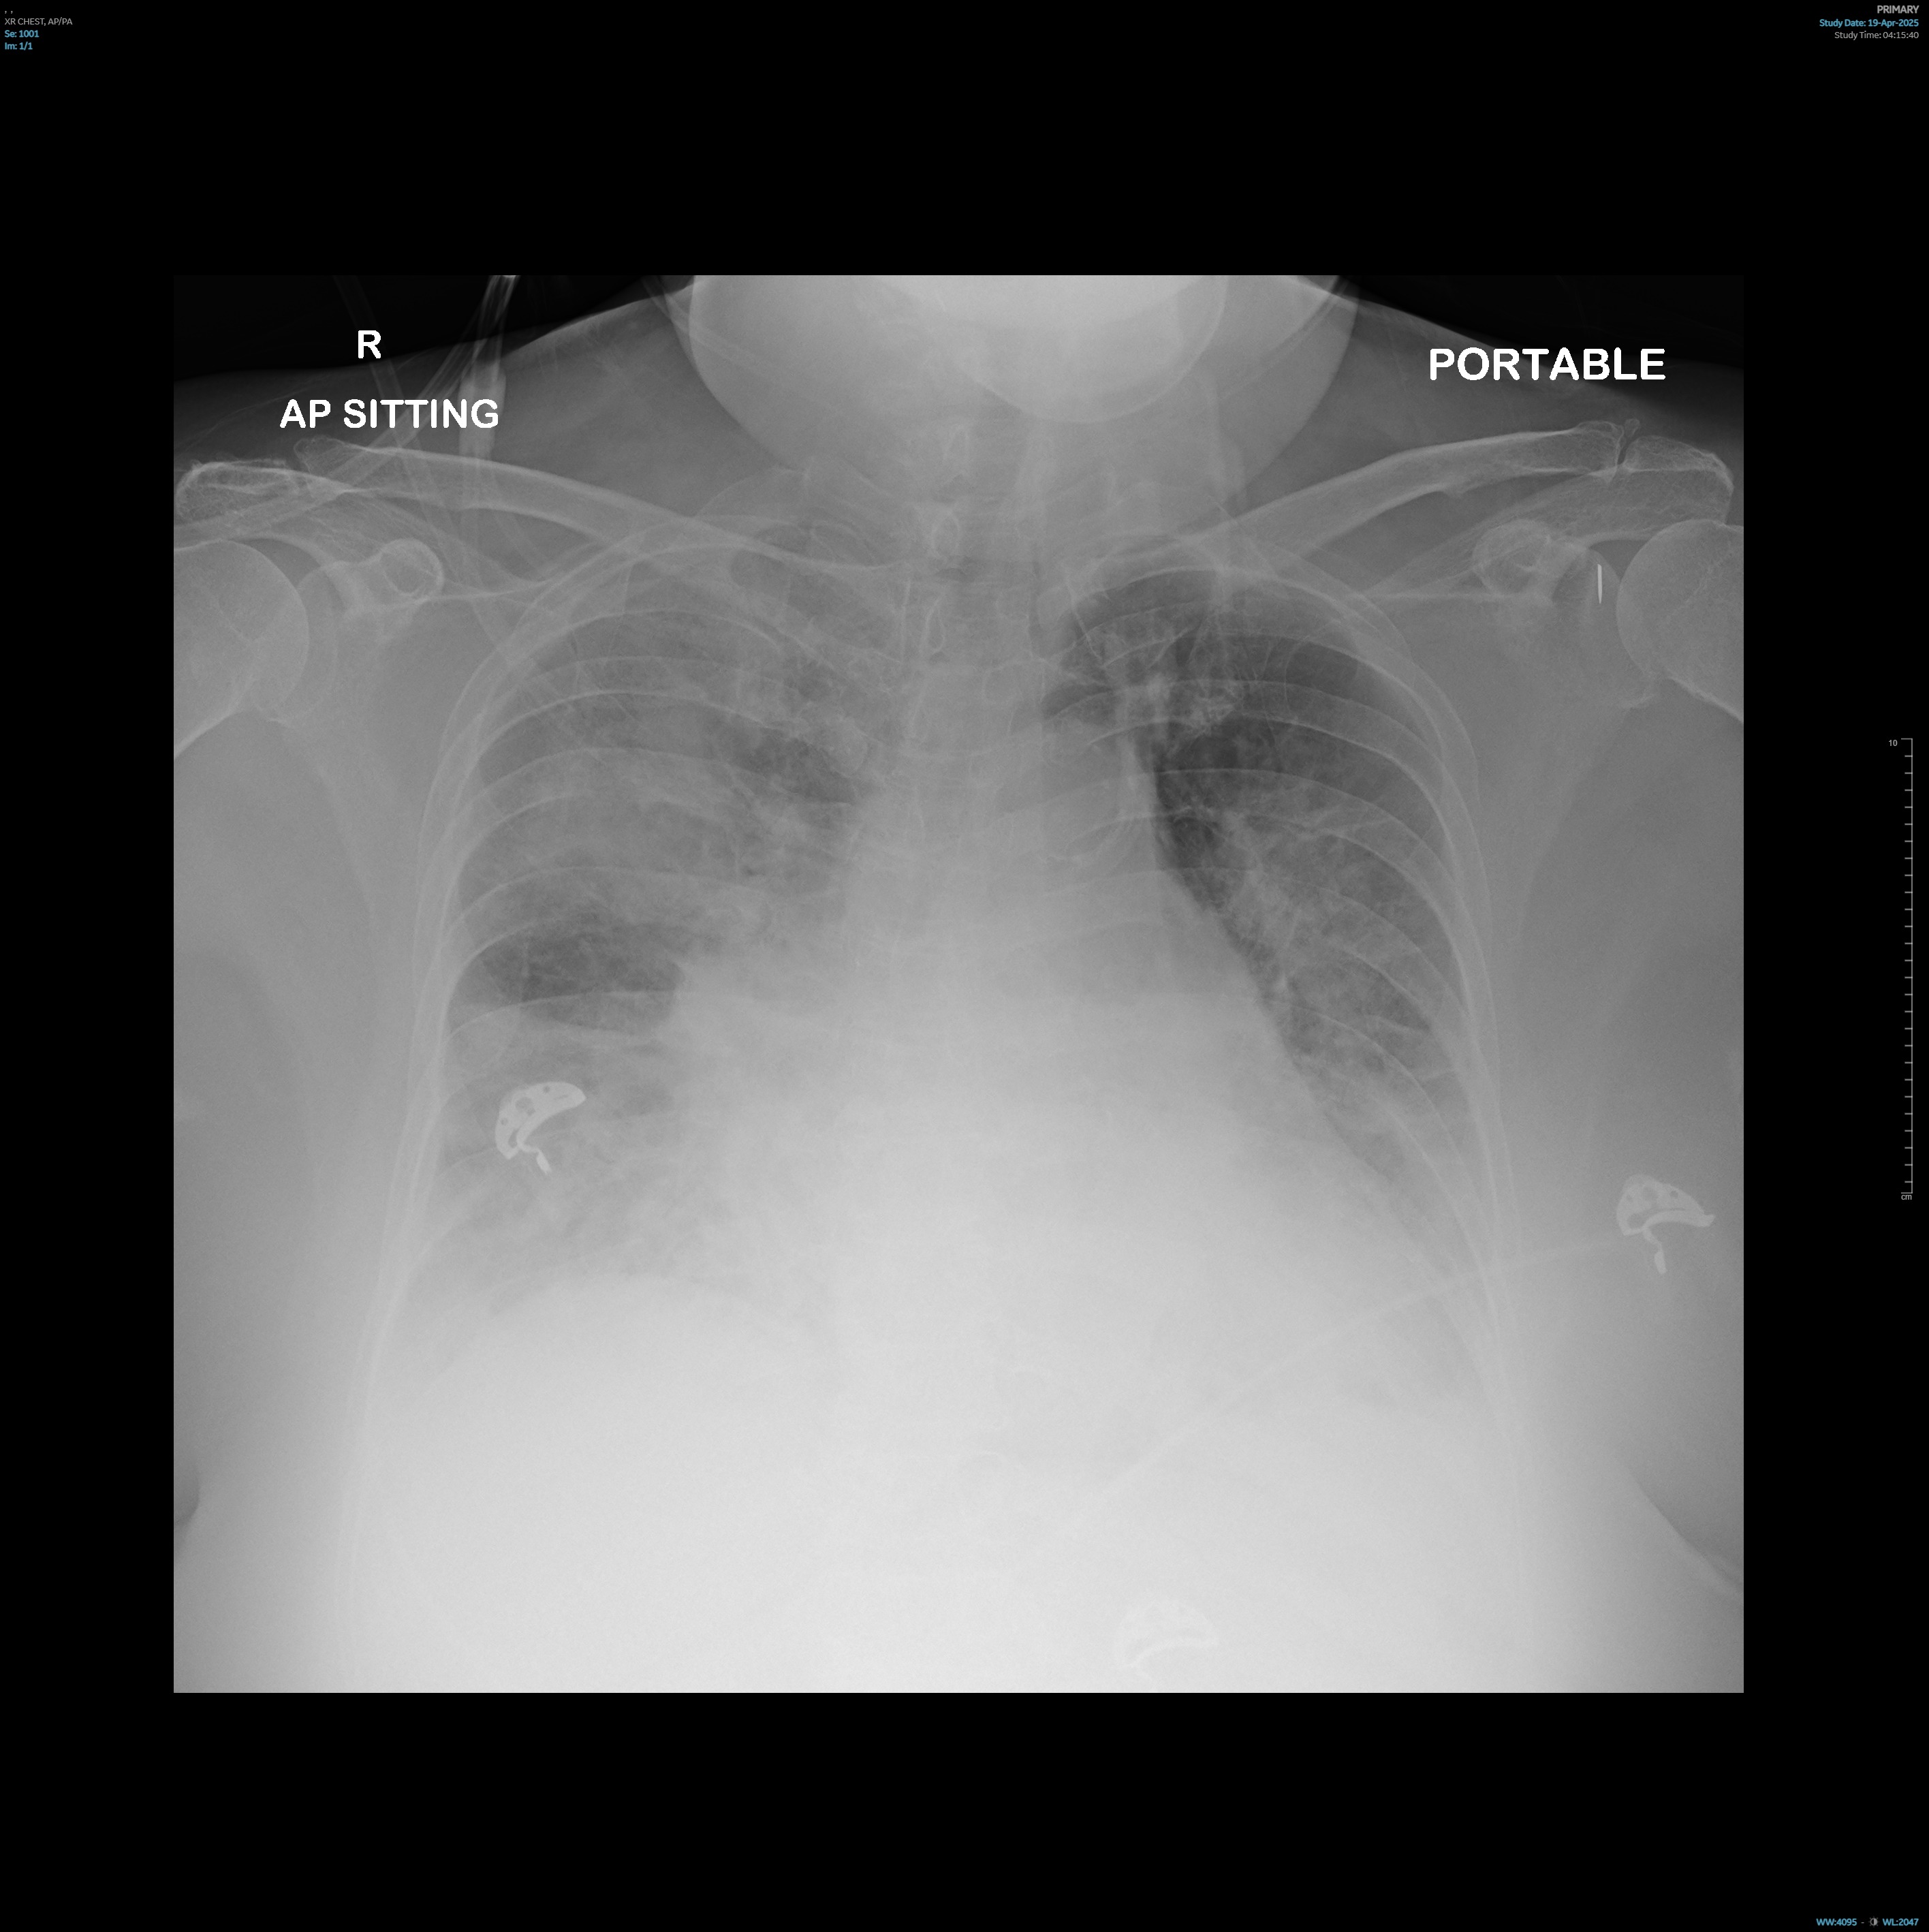

Troponin T continued to uptrend post-intubation and repeat12-lead electrocardiogram (ECG) showed worsening widespread depressions withAVR elevation. Chest X-Ray post-intubation showed rapidly worsening bilateralinfiltrates compared to admission. Bedside ultrasound showed a severely reducedleft ventricular ejection fraction.